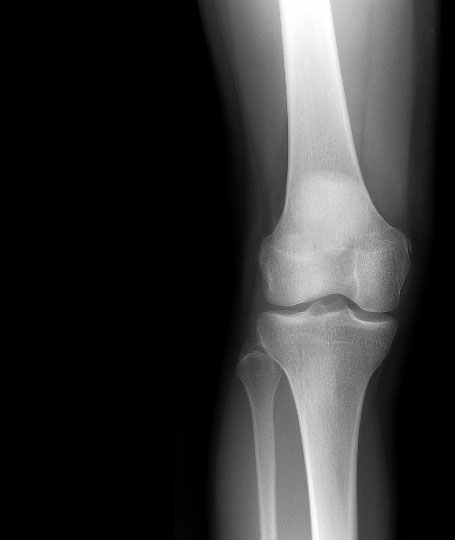

• Femur

• Fibula

• Intercondylar Fossa

• Lateral Femoral Condyle

• Lateral Femoral Epicondyle

• Lateral Intercondylar Eminence

• Lateral Tibial Condyle

• Medial Femoral Condyle

• Medial Femoral Epicondyle

• Medial Intercondylar Eminence

• Medial Tibial Condyle

• Patella

• Tibia

• Tibial Plateau